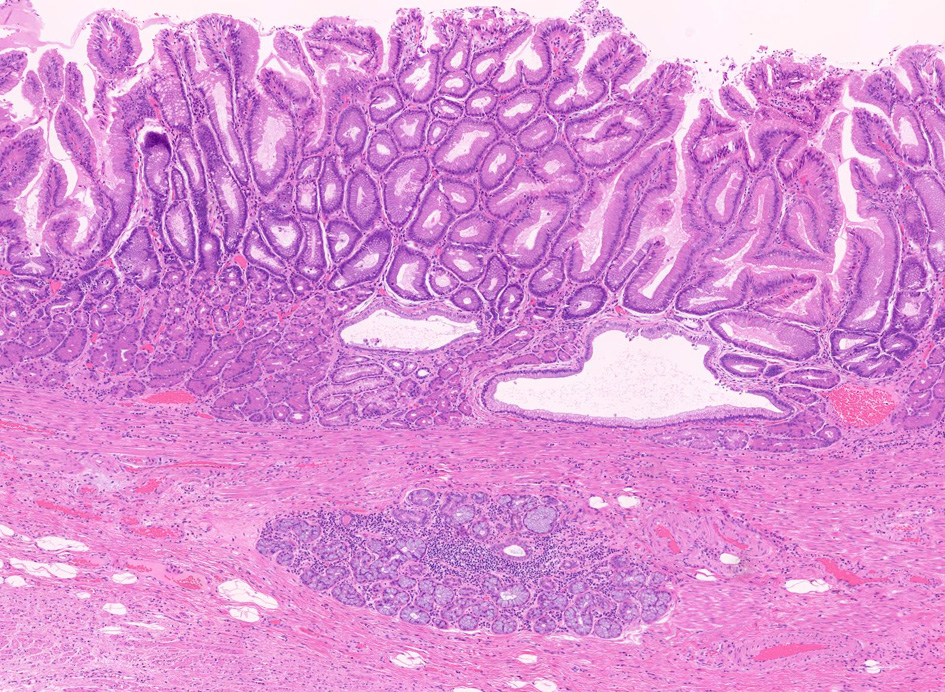

Fig.1 Barrett食道 腺癌Fig.2 EGP

1. 固有食道腺と導管が円柱上皮部位に存在する確定診断

2. 円柱上皮下の粘膜筋板二重化:かなり確実な所見,8割はあたり

EGPは常に扁平上皮から誘導されてできる腺で, その存在は必ず一度は粘膜内に扁平上皮があったという印であり食道固有の構造である。

扁平上皮島連続切片の観察では,すべての扁平上皮島は固有食道腺と導管を介して結合している

固有食道腺の開口部は必ず扁平上皮で囲まれており, 食道腺の上皮が進展しBarrett上皮ができるとする由来説は誤りである。